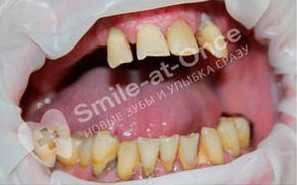

Чорный Станислав Владимирович: портфолио (25)

Имплантация

Для восстановления жевательных зубов потребовалось проведение имплантация полной челюсти по причине плохого состояния зубов на всей челюсти.